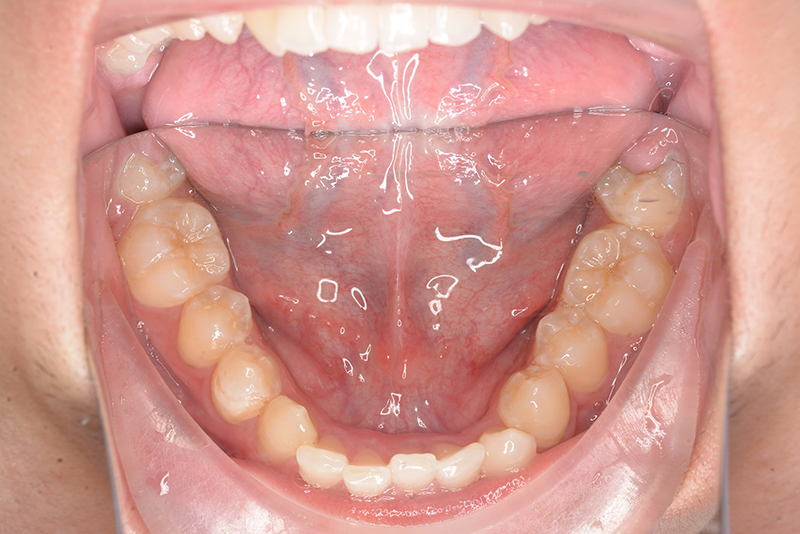

動的治療終了時

FP・IOP

批評・予后 側貌はconcave typeであり、下顎歯列は叢生が少ないこと、右上3欠損、左右上2は矮小歯であることを考慮して右上C、左側2抜歯とした。治療後はアンテリアレシオの調和を図るべく右上2は暫間的修復(CR)にて歯冠幅径を大きくしている。保定終了後には同部位は最終補綴を装着する予定である。